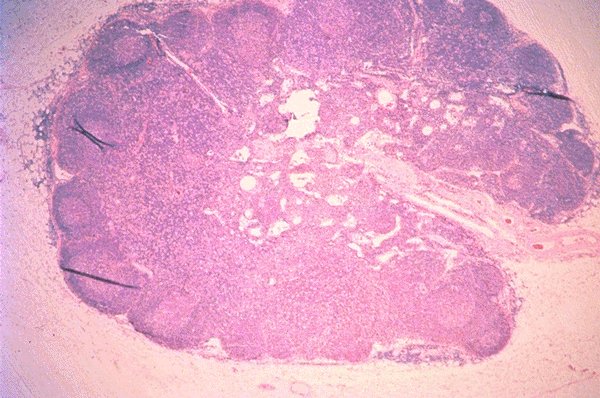

An extremely low power view of an H&E stained

lymph node is seen in this photomicrograph.

Follicles are noted in the cortical area and these

are differentiated from the non-follicular portions

of the node. Vascular structures are also seen.